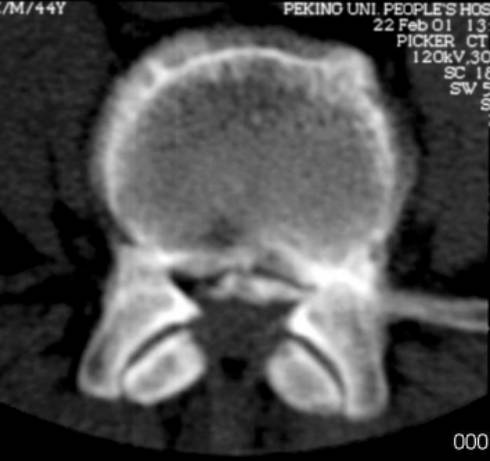

3、CT检查:可取之处在于可准确显示异常组织的性质,直接显示椎间盘突出的真实性质和范围。可清楚地显示椎管横断面的骨性结构,对侧隐窝狭窄,黄韧带肥厚,椎间关节病变及神经孔周围极外型椎间盘突出的显示有独特的临床价值。

但此检查不足之处在于对软组织分辨率低,不能直接进行矢状面、斜面扫描。对纤维环膨出显示较模糊,有假阳性情况。

椎体后方静脉孔处的骨质间隔,不要误认为后纵韧带骨化

椎管狭窄并间盘突出

椎管狭窄

中央性椎管狭窄

侧隐窝狭窄